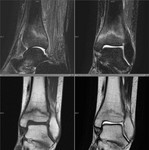

[画像診断]疲労骨折のMRI 2010-04-22

2010-04-22

[画像診断]疲労骨折のMRI

(詳細は「タカ派の画像診断医」へ)